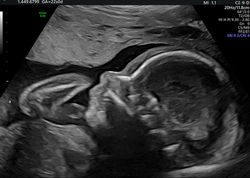

Toutes les échographies de première intention peuvent être réalisées au cabinet: datation, premier, second et troisième trimestre.

Mais aussi les échographies gémellaires, surveillance de croissance et doppler maternel et foetal, mesure du col.